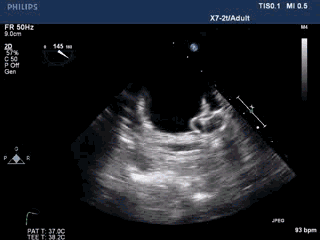

手术过程—左心耳造影选择封堵器

术中TEE双平面及DSA造影显示,梳状肌发达,延伸至心耳口部。

DSA造影显示LAA开口直径18mm,深26mm,拟采用24mm Watchman封堵器。